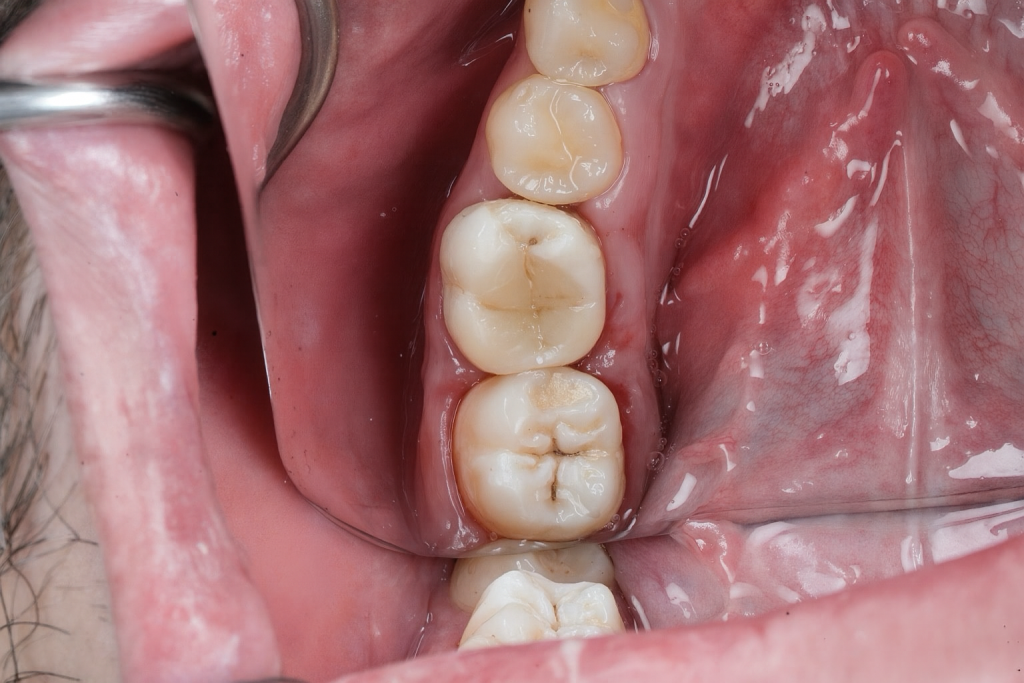

7️⃣ Finishing and Polishing

Anatomical morphology refined with Sof-Lex discs and composite finishing burs. Final enamel gloss achieved using Lucida Polish (Style Italiano) (Fig 7).

- Fig 7: Final morphology and occlusal finish.